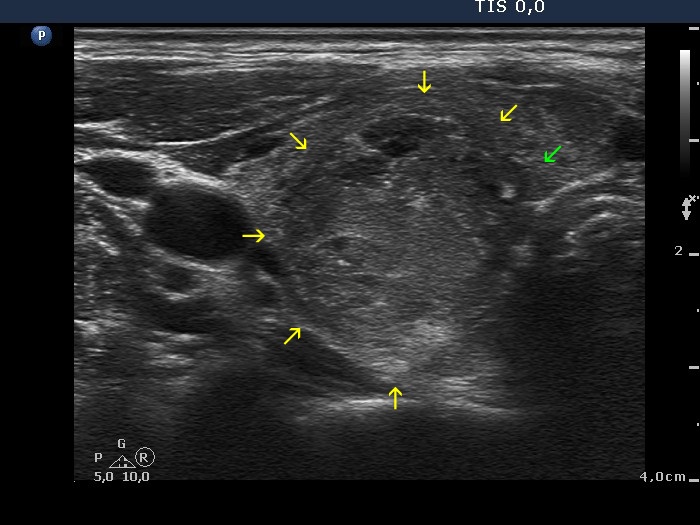

Papillary carcinoma (histology) - case conp014

Transverse scan

Longitudinal scan

This is not a decisive but only a suspicious pattern. Lower to the main body of the tumor, there are several microcalcifications (yellow arrows). The presence of these isolated microcalcifications raises the possibility of infiltrative spread of the tumor. Although the less hypoechogenic area pointed with red arrows dorsal to the tumor might be also presentation of extrathyroidal spread, such pattern has limited if any relevance; a focus of thyroiditis might be also the cause. Be aware that the main difference between the non-specific finding in the left image and the suspicious pattern in the right image is based on the lack (left) and the presence (right) of microcalcifications. The possibility of extrathyroidal spread should be also considered: the ventral part of the nodule cannot be distinguished from the strap muscle running on the ventral surface of the lobe.